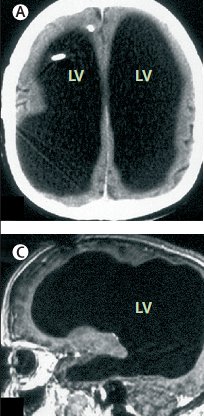

Wiele osób czytało, że szkocki matematyk z wodogłowiem pomimo braku kory mózgu wykazywał inteligencję wyższą od przeciętnej ... ale czy na pewno?

Skąd to wiedzą? Z gazet! Czy gazeta prawdę Ci powie, czy raczej szuka sensacji?

Grupa "urban myth" wytropiła źródło tej informacji - jest to typowy mit miejski, oparty na pomyłce (nie ten mózg ...), ale czy ktoś chce to wiedzieć? Najpierw sprawdzajmy w

legendach miejskich ...

Wiadomość prawdziwa (Lancet 370, 2007, pp. 262) oraz jej skrót w New Scientist: wodogłowie spowodowało u 44-letniego urzędnika z Francji rozprzestrzenienie się płynu mózgowo-rdzeniowego, wypierającego mózgu w kierunku ścianek czaszki. Jak to możliwe, że nikt nie zauważył problemów? Zmiany następowały powoli, odruchy i schematy postępowania nie zanikły, ale IQ spadło do poziomu 70 punktów ... Nie ma tu więc rewelacji.